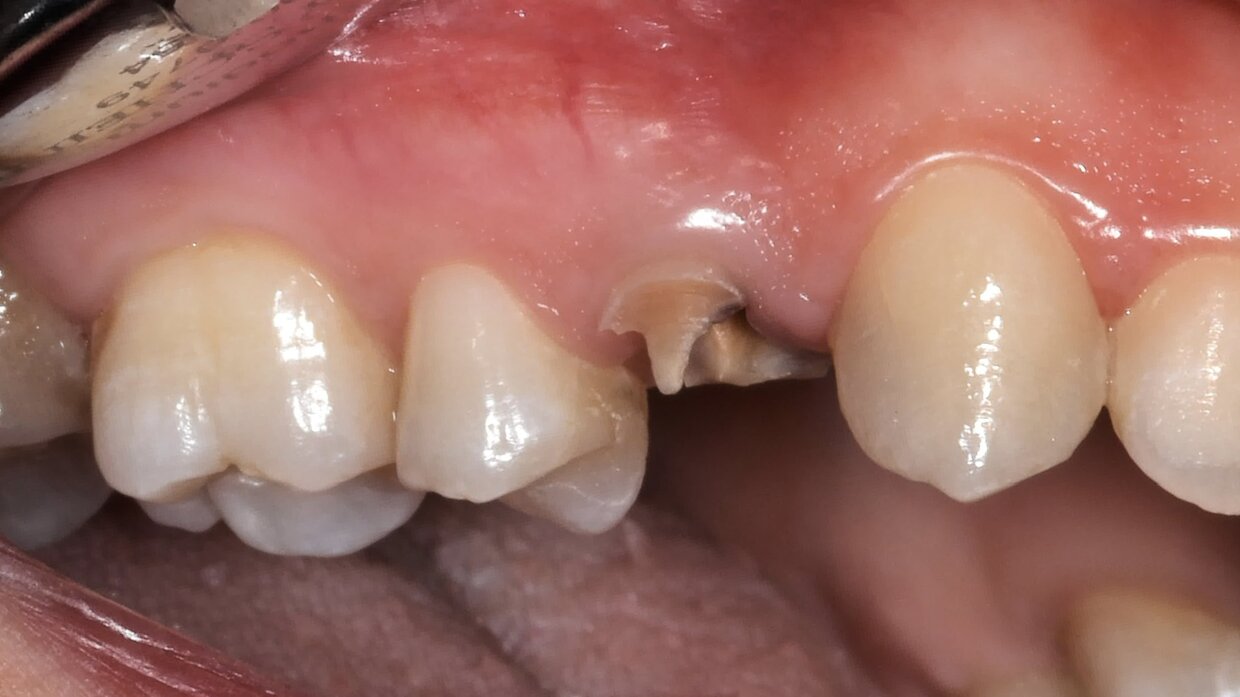

Il posizionamento degli impianti è stato pianificato prima dell'intervento su un software dedicato. In un'unica seduta, dopo l'estrazione degli elementi dentari compromessi, sono stati immediatamente inseriti gli impianti nella posizione pianificata, grazie alla realizzazione della dima chirurgica. Per ridurre il riassorbimento osseo a lungo termine e garantire quindi una maggiore resa estetica (vista la zona d'intervento), la chirurgia è stata eseguita con una particolare tecnica denominata: Socket Shield Technique.